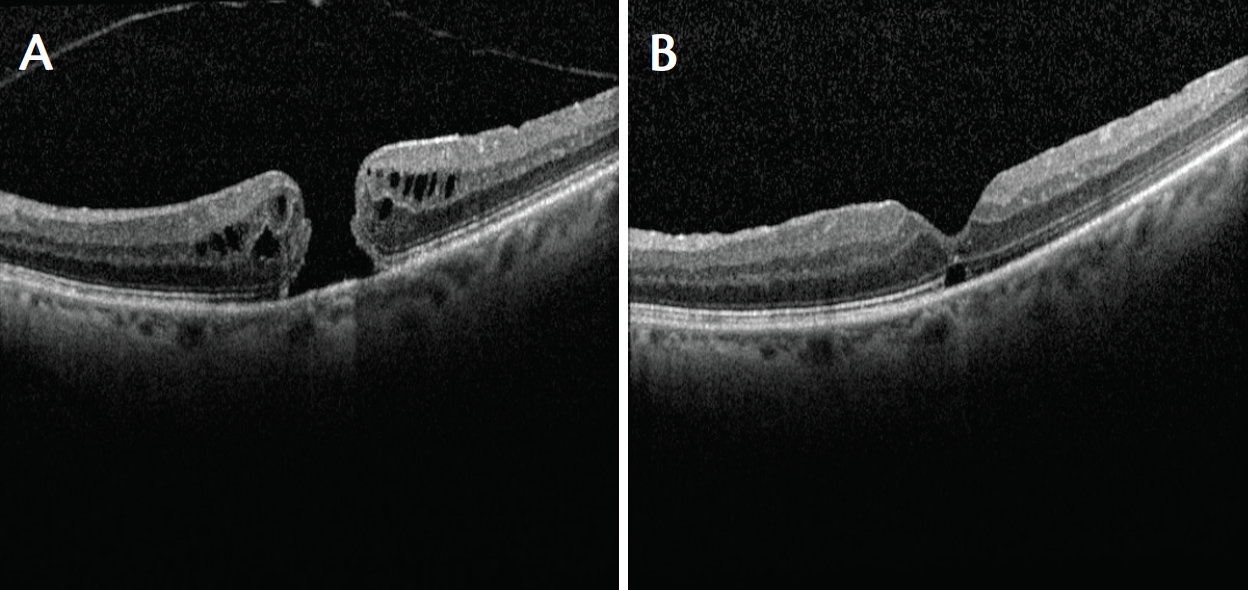

Case No. 3

A 68-year-old-man underwent macular hole repair with vitrectomy, ILM peeling, and gas tamponade. The hole did not close, and visual acuity in the affected eye was 20/200 (Figure 3A). The patient underwent repeat vitrectomy with an ILM patch and silicone oil tamponade. The hole closed, and his visual acuity had improved to 20/80 at 4 months after surgery and after silicone oil removal (Figure 3B).

Figure 3. Case No. 3: Open macular hole despite previous surgical repair. Visual acuity 20/200 (A). Patient underwent repeat vitrectomy with ILM patch and silicone oil tamponade. The hole closed, and visual acuity improved to 20/80 at 4 months after surgery and after silicone oil removal (B).